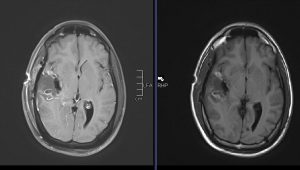

Χωροκατακτητική Εξεργασία δεξιού Κροταφικού Λοβού